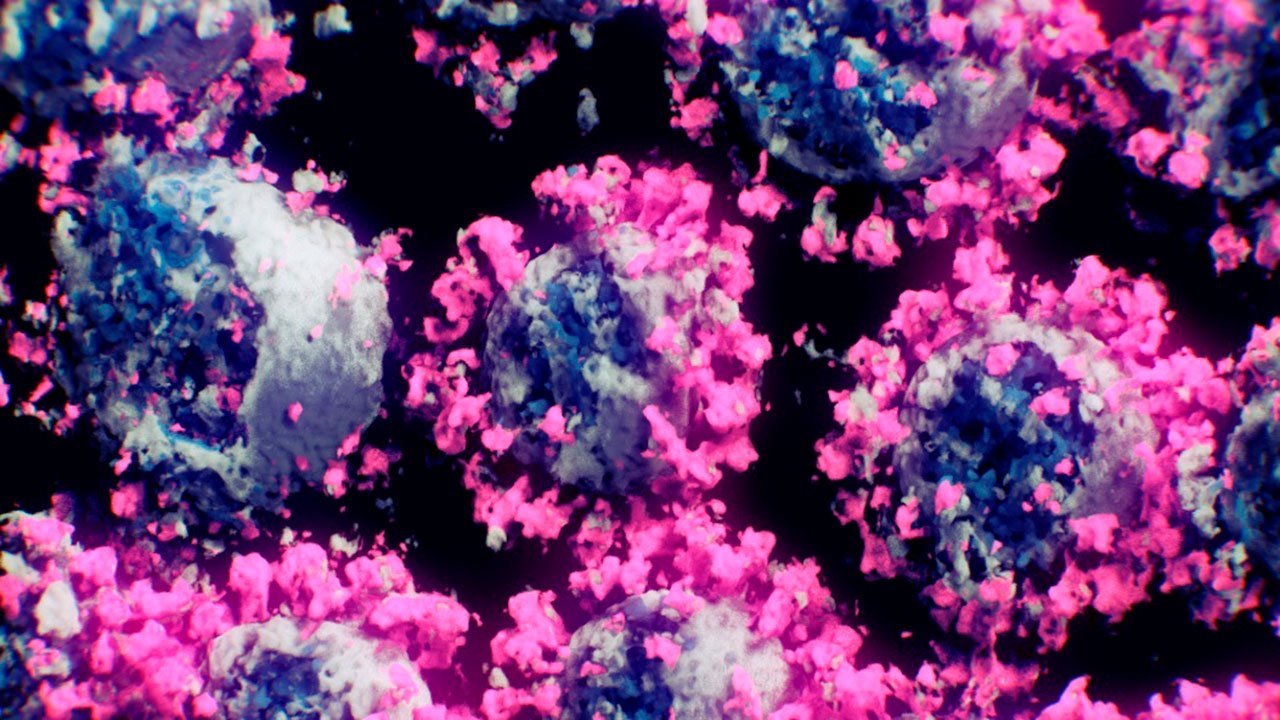

El material genético del SARS-CoV-2, el coronavirus que causa la enfermedad de Covid-19, se llama ácido ribonucleico (ARN). Para replicarse y, por lo tanto, establecer la infección, el ARN del SARS-CoV-2 debe secuestrar una célula huésped y utilizar la maquinaria de la célula para duplicarse.

Los errores ocurren a menudo durante el proceso de duplicación del ARN viral, dando como resultado virus que son similares pero no copias exactas del virus original. Estos errores en el ARN viral se denominan mutaciones y los virus con estas mutaciones se denominan variantes. Las variantes pueden diferir por una sola o muchas mutaciones.

Una variante se denomina cepa cuando muestra propiedades físicas distintas. En pocas palabras, una cepa es una variante que se construye de manera diferente y, por lo tanto, se comporta de manera diferente al virus original. Estas diferencias de comportamiento pueden ser sutiles u obvias.